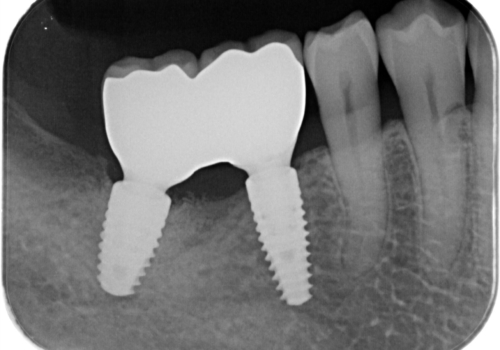

上顎は歯根破折と排膿が認められ、下顎も骨吸収により残せる状態ではないと判断し、抜歯後にインプラント治療(右上567、右下67)を行うことになりました。

骨吸収により上顎の骨量が少なかったため、インプラント埋入時にソケットリフトで骨補填材を填入も行いました。